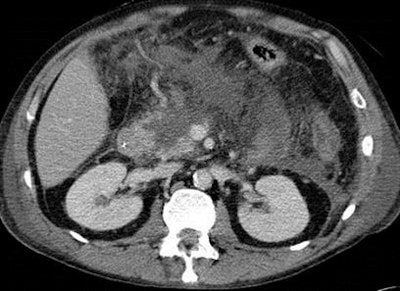

He illustrated his point with an example of a patient who was assumed to have interstitial disease when a CT scan was carried out on day one, but was found to have extended necrosis of the pancreas on day three. The patient subsequently died on day five.

Imaging in acute pancreatitis is not without its pitfalls, he continued. In particular, central gland necrosis, a subtype of necrotizing pancreatitis, is important because it enables valuable prognostic information on a day-three scan.

"If I see a patient with midgland necrosis and significant remaining viable pancreatic tail, I tell the surgeon or clinician that this patient has a high chance of intervention somewhere during the course of their disease. In more than 90% of these patients, increasing collections are observed on serial CTs that require intervention," Bollen noted.

Finally, he explained that central gland necrosis is associated with pancreatic duct disruption, especially if the necrosis extends over two centimeters.